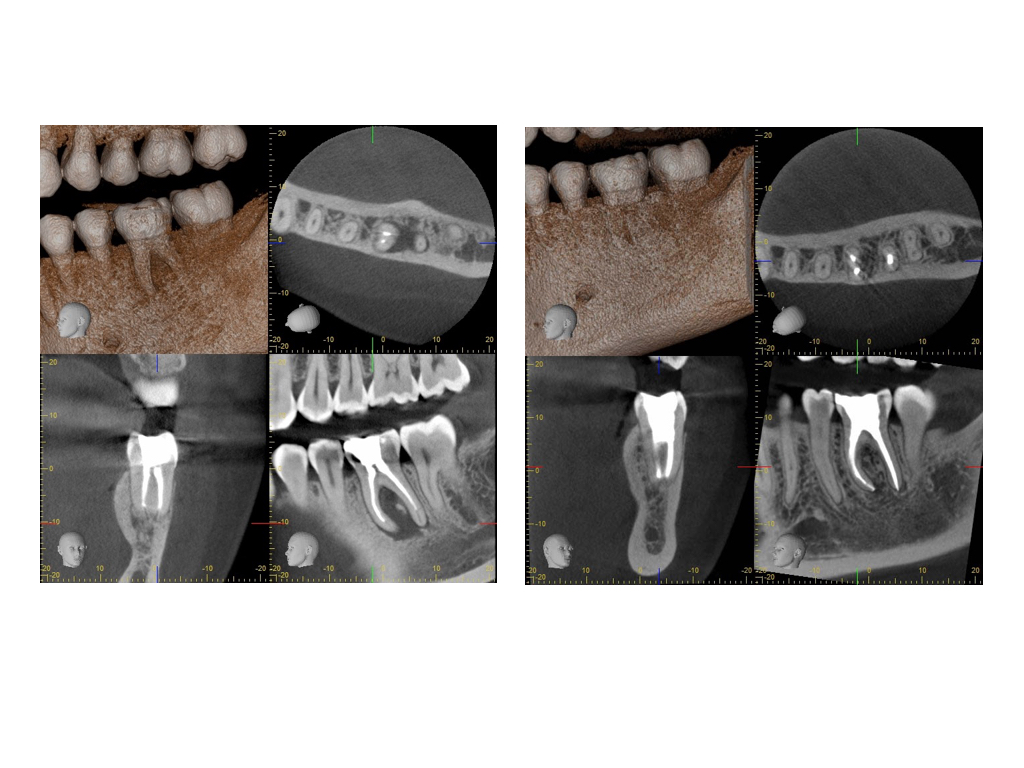

TS_36.010

Calciumhydroxid – Überpressung (1)